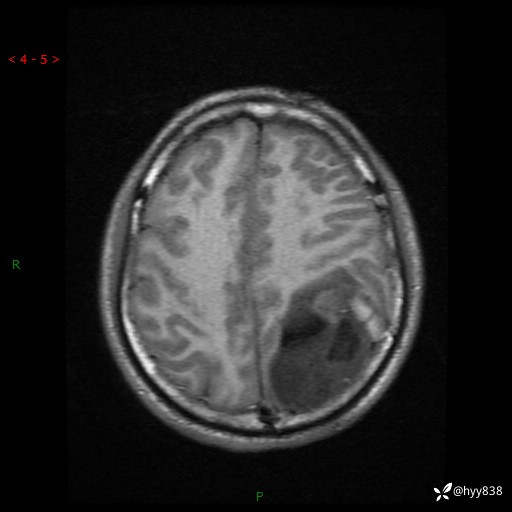

病例年轻小伙,头痛伴呕吐半年,渐进性加重1月。疑难病例,第一次见--结果公布~

性别:男

年龄:21岁

简要病史:头痛伴呕吐半年,渐进性加重1月

颅脑MRI平扫+增强